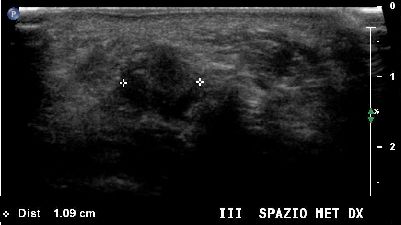

Neuroma di Morton del terzo spazio intermetatarsale (img. 01) Neuroma Morton 01